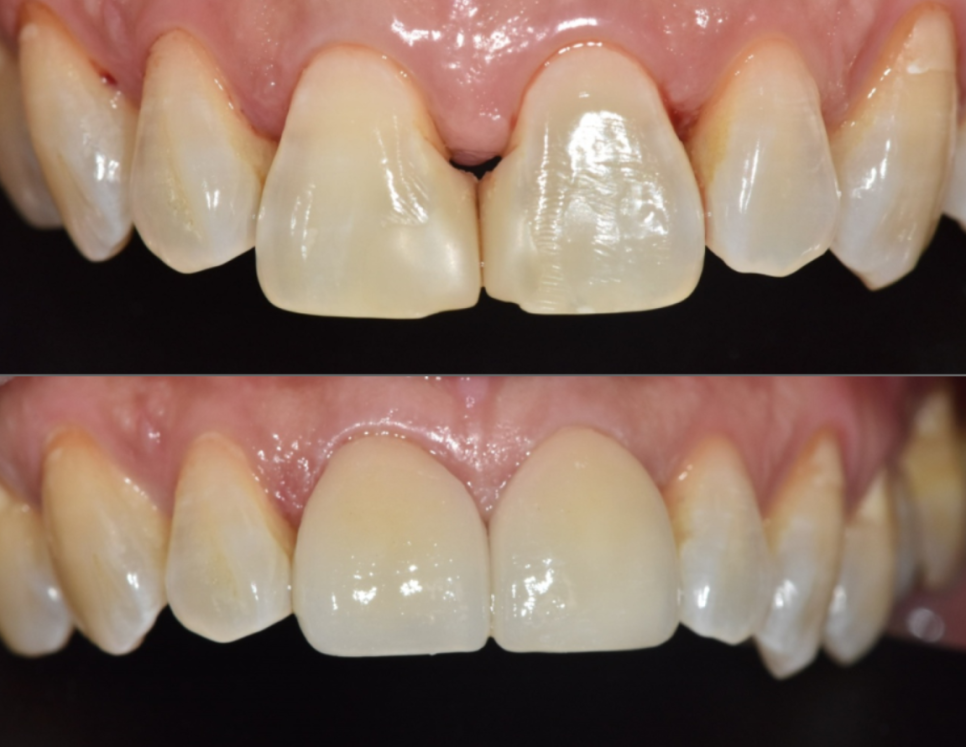

250318

이 환자분 역시

치아 색감과 투명도에 대해

세밀한 의견을 주셨고,

250318 (전) 250325 (후)

즉각적인 피드백을 반영해

자연스럽고 조화로운 앞니 라인이

완성되었습니다. ^^

앞니 사이 틈과 치아 변색은

단순히 관리가 부족해서 생긴 문제가 아니라,

노화와 과거 치료 이력이

함께 작용해 나타나는 변화인 경우가 많습니다.

치아도 몸처럼,

나이가 들면 ‘관리만으로는 부족한 시점’이

생길 수 있습니다.

이럴 때 현재 치아 상태에 맞는 치료 선택이

무엇보다 중요합니다.